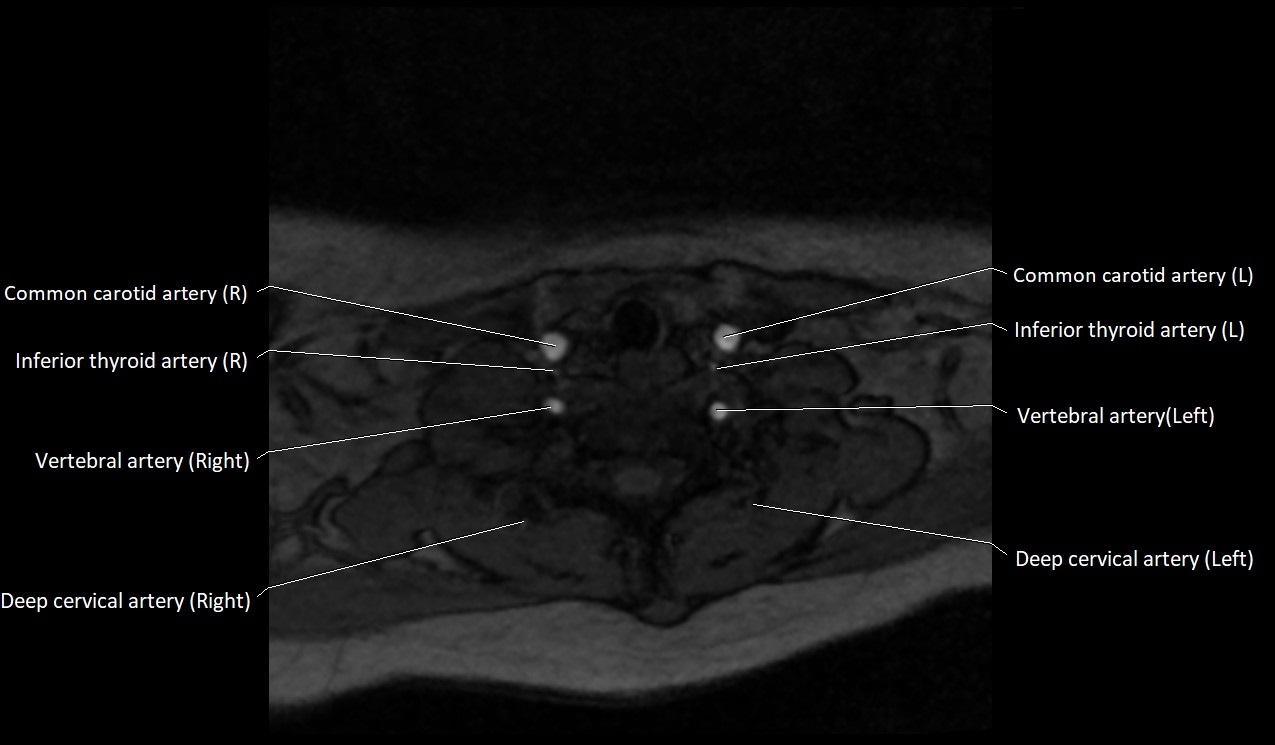

MRI images

image